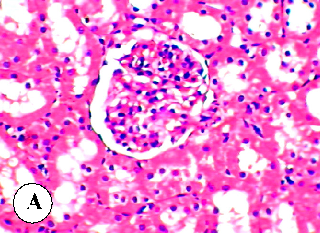

Figure 4

Figure 4 Micrograph

Histopathological examination of liver tissue from control rats, showing normal hepatic architecture for baseline comparison with diazinon-treated groups.

Protective effect of some plant oils on diazinon induced hepatorenal toxicity in …